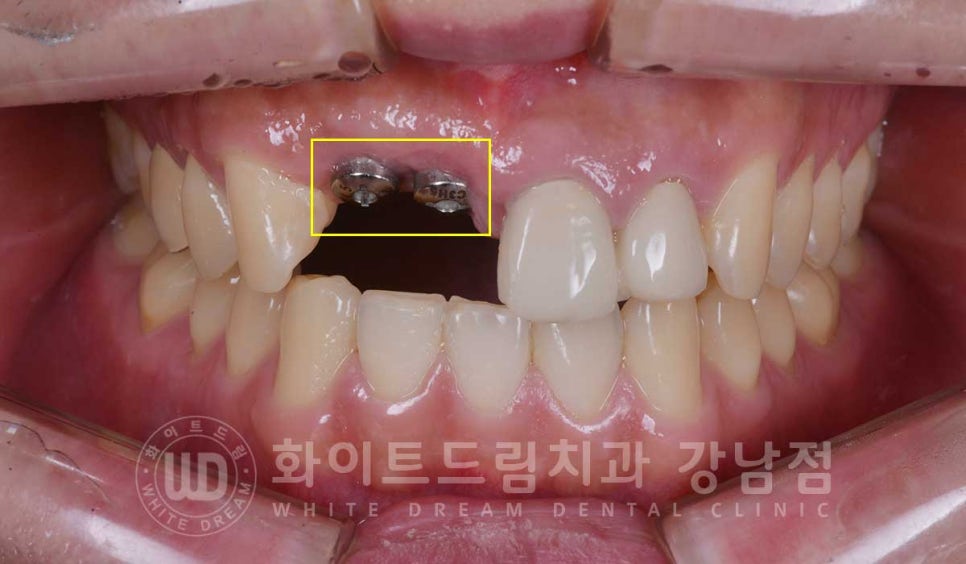

수술 당시 사진입니다.

▲ 앞니 임플란트 수술일자 : 23.05.04

2차 수술 시 체결하는 힐링 어버트먼트까지 체결된 것이 확인됩니다.

2차 수술까지 한 번에 진행할 때는 이렇게 잇몸의 높이와 힐링 어버트먼트가 같은 높이에 있어야

잇몸이 예쁘게 잘 아물게 된답니다.